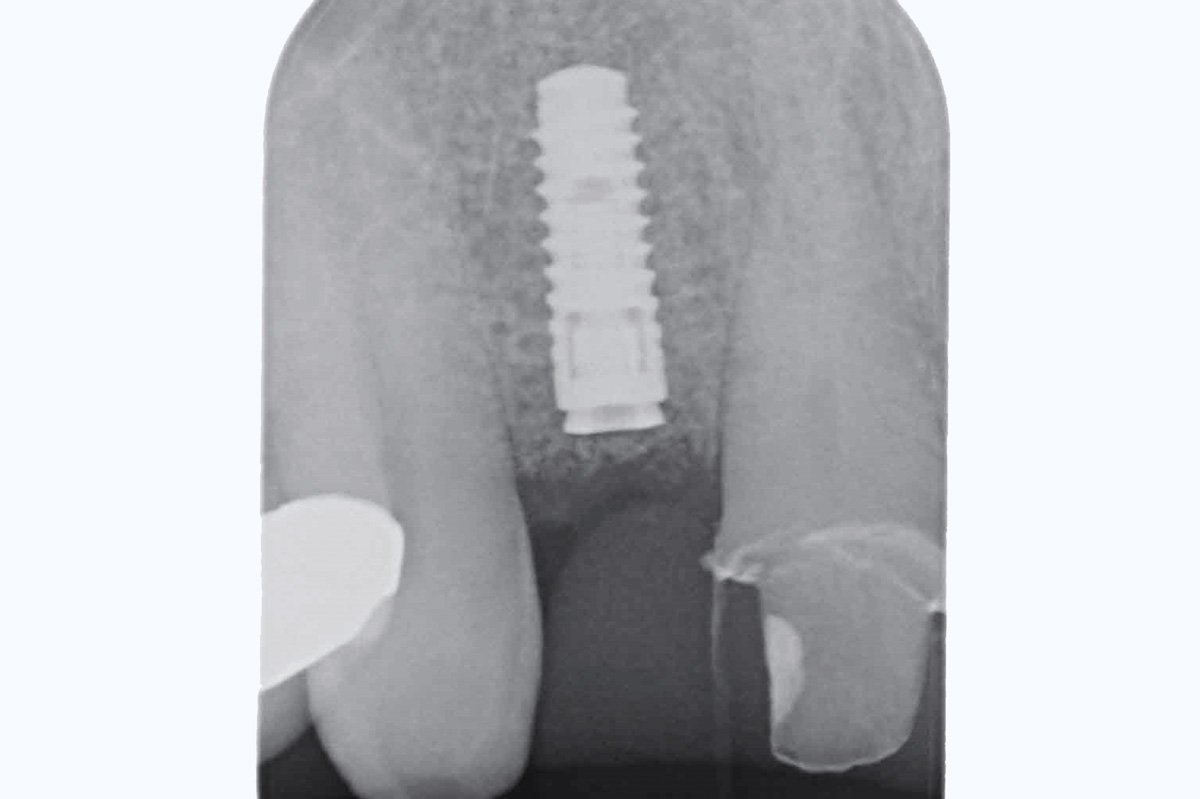

2/19 - Initial situation: x-rayBone augementation with maxresorb® - Dr. R. Cutts

18/19 - X-ray at final restorationBone augementation with maxresorb® - Dr. R. Cutts